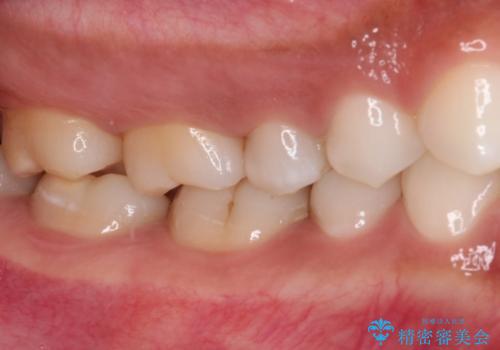

奥歯のむし歯をゴールドインレーで修復

奥で目立たないことから、虫歯の再発リスクが最も低く、咬合力による歯への負担も少ないゴールドインレー(PGAインレー、白金加金インレー)にて修復治療をすることとしました。

ゴールドインレーは銀歯のインレーやセラミックインレーと比べ、「技工操作の精度が高く、適合が著しく良い」というメリットがあります。特に上の奥歯は歯科医師の操作が行いにくいため、「適合の良さ」は再治療のリスクを防ぐ上でとても重要な要素となります。

上の奥歯は金属色が見えることもないため、審美的な問題は全くありません。